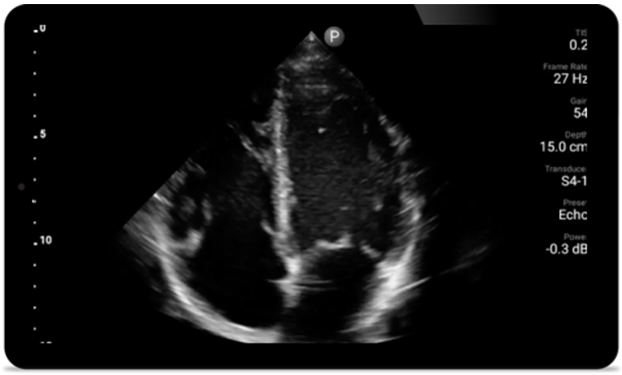

Lumify S4-1 broadband phased array transducer

• 4 to 1 MHz extended operating frequency range

• 2D, color Doppler, M-mode, advanced XRES and multivariate harmonic imaging

• High-resolution imaging for abdominal and cardiac applications: Cardiac, OB/GYN, Lung, Abdomen and FAST imaging preset optimizations Lumify aids life-saving technology in prehospital setting